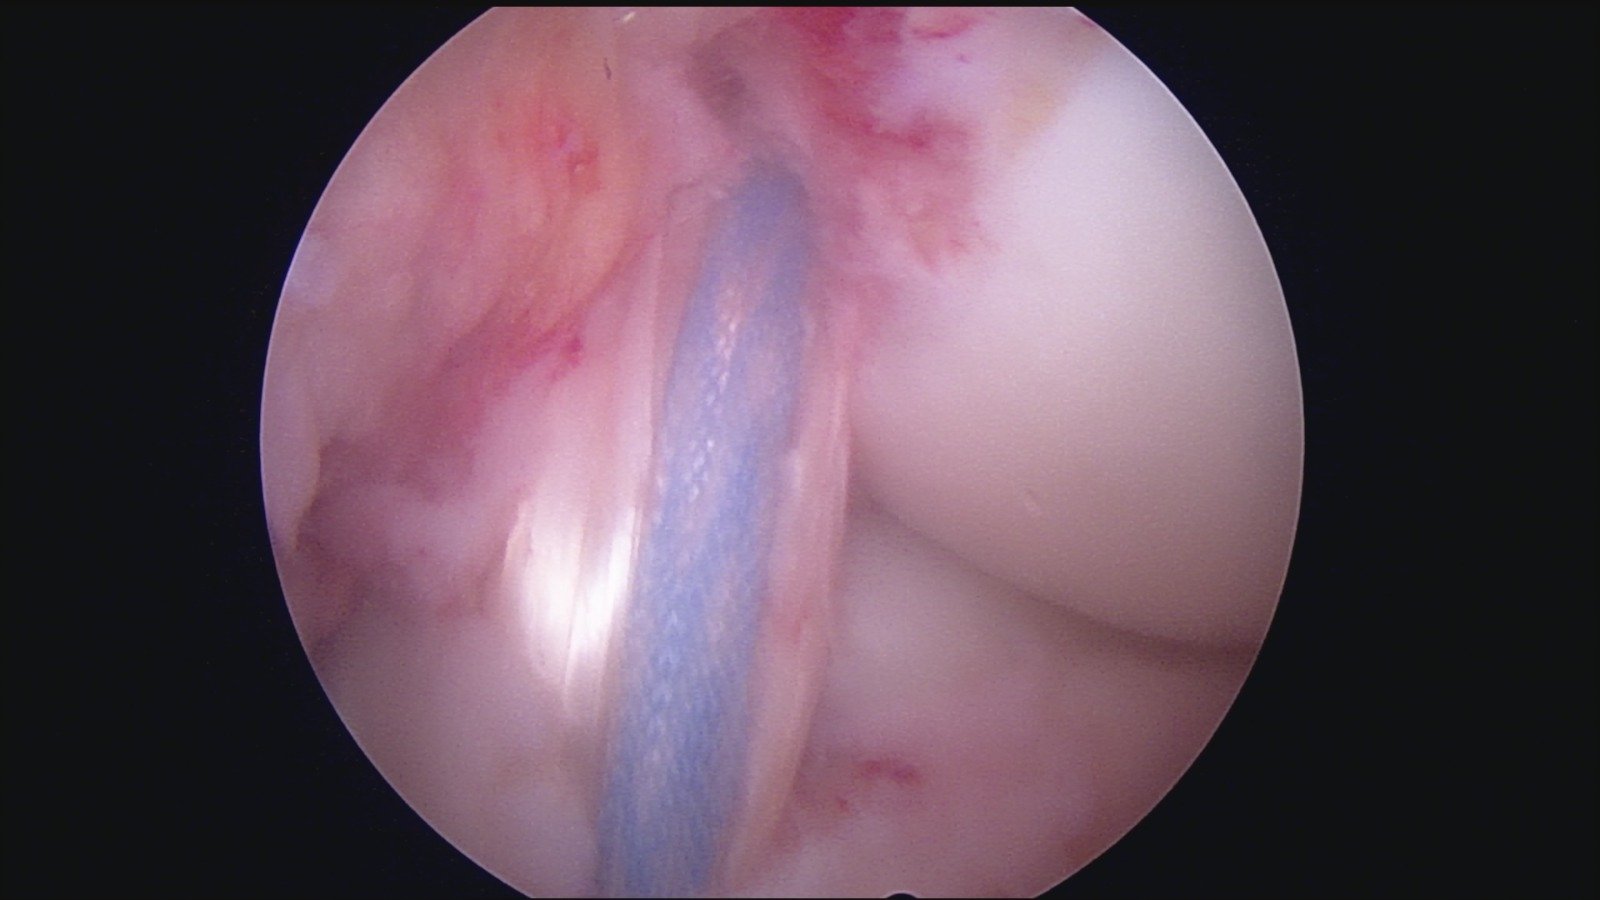

GalleryShoulder rotator cuff repair Meniscus root repair Meniscus repair Bankart repair for recurrent shoulder dislocation ACL reconstruction Machines Instruments